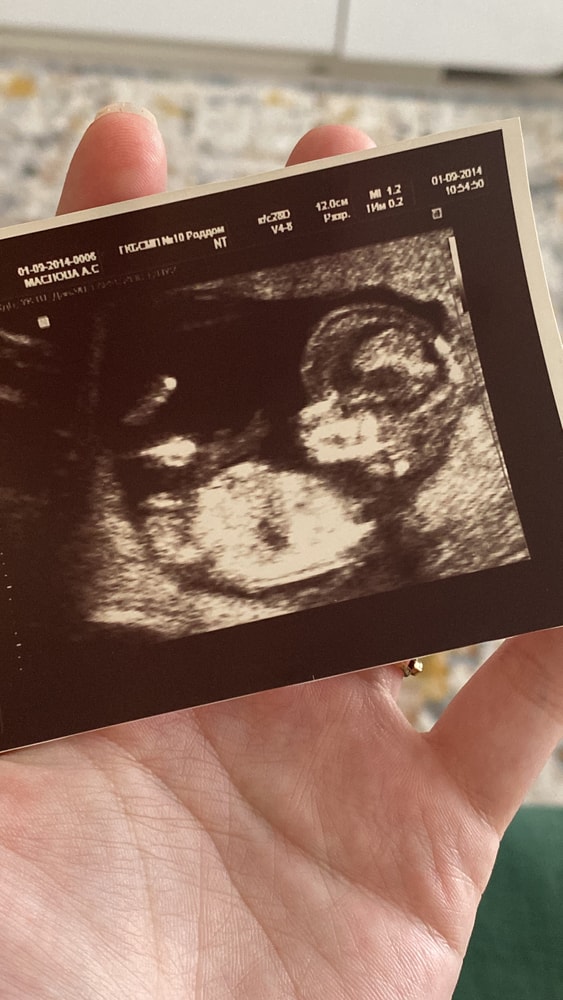

Половой бугорок в 12 недель и 6 дней. Видно?

Светлана , то что вы и обвели. На моем узи +- тоже самое было. Девочку ждём

Алина, но на 1 фото я вижу девочку 😄

Светлана , на самом первом видно.